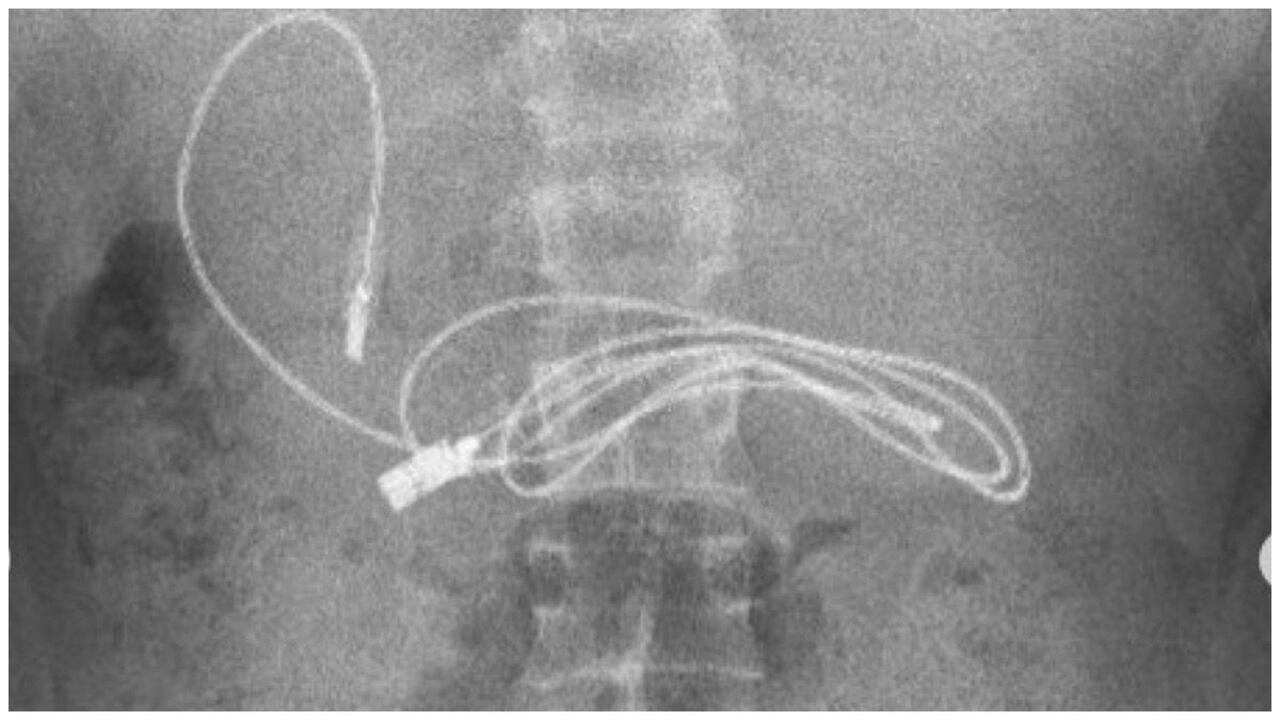

Esta curiosa historia se presentó en Diyarbakir, Turquía, donde el preadolescente presentaba dolor y náuseas. Cuando los médicos vieron las imágenes internas de su torso, se percataron de que en su estómago estaba alojado un cargador USB.

El gastroenterólogo pediátrico Yasar Dogan fue quien se encargó de la situación. Además, por medio de sus redes sociales compartió las impresionantes imágenes que comprueban la situación vivida por su paciente.

El profesional de la salud tomó la decisión de realzar un procedimiento con endoscopio para poder a través de la boca y el conducto gástrico llegar hasta donde se encontraba alojado el cargador de celular. Cuando por fin se logró hacer contacto con el objeto, el doctor Dogan se percató de que también había una banda elástica para cabello junto al cargador.

“Obviamente, tuvimos dificultades para quitar el cable, ya que un extremo del cable había pasado al intestino delgado (...) Después de que el procedimiento concluyó con éxito, el paciente fue enviado a casa con buena salud”, explicó el doctor Yasar Dogan.